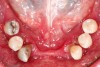

The patient’s mandibular arch included six remaining teeth and an interim partial denture.

Fig 2